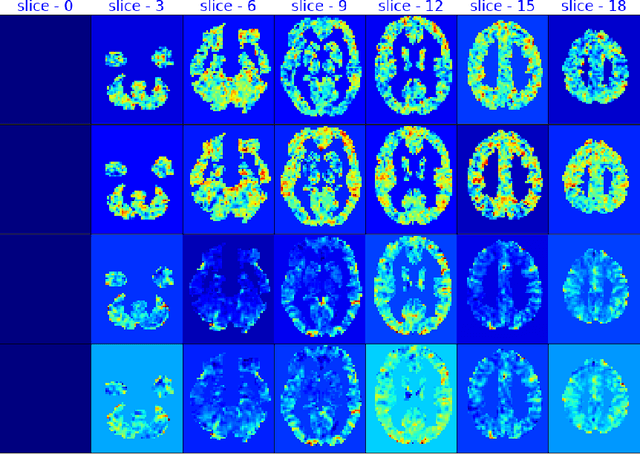

Abstract:fMRI semantic category understanding using linguistic encoding models attempt to learn a forward mapping that relates stimuli to the corresponding brain activation. Classical encoding models use linear multi-variate methods to predict the brain activation (all voxels) given the stimulus. However, these methods essentially assume multiple regions as one large uniform region or several independent regions, ignoring connections among them. In this paper, we present a mixture of experts-based model where a group of experts captures brain activity patterns related to particular regions of interest (ROI) and also show the discrimination across different experts. The model is trained word stimuli encoded as 25-dimensional feature vectors as input and the corresponding brain responses as output. Given a new word (25-dimensional feature vector), it predicts the entire brain activation as the linear combination of multiple experts brain activations. We argue that each expert learns a certain region of brain activations corresponding to its category of words, which solves the problem of identifying the regions with a simple encoding model. We showcase that proposed mixture of experts-based model indeed learns region-based experts to predict the brain activations with high spatial accuracy.